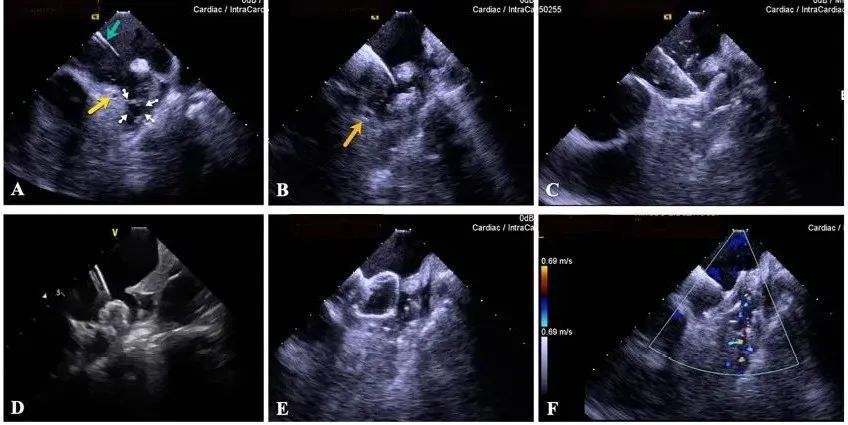

一種與心導(dǎo)管檢查相結(jié)合的超聲心動(dòng)圖診斷新興技術(shù),通過將超聲探頭置于心腔內(nèi)部,發(fā)射并接收超聲信號(hào),來精確獲取心臟解剖結(jié)構(gòu)、心臟血流動(dòng)力學(xué)等信息的實(shí)時(shí)成像。與其他影像技術(shù)相比,ICE技術(shù)具有操作簡單、無輻射、安全性高、手術(shù)效率高、實(shí)用等優(yōu)勢(shì),ICE在很大程度上有望取代經(jīng)食道超聲心動(dòng)圖(TEE),成為電生理和結(jié)構(gòu)性心臟病領(lǐng)域的理想成像方式。

目前ICE技術(shù)已被應(yīng)用于左心耳封堵、房顫射頻消融、二尖瓣成形、房間隔缺損封堵等多種心臟介入手術(shù),應(yīng)用場景主要圍繞臟電生理、結(jié)構(gòu)性心臟病等領(lǐng)域,目前以電生理應(yīng)用為主。數(shù)據(jù)顯示,我國結(jié)構(gòu)性心臟病介入器械市場規(guī)模已從2017年的4億元增長至2021年的20億元,年復(fù)合增長率達(dá)48.3%;預(yù)計(jì)到2025年,該市場規(guī)模將達(dá)到104億元,可以預(yù)見ICE市場規(guī)模也將同步高速增長,未來市場發(fā)展空間廣闊。

心腔內(nèi)超聲(ICE)技術(shù)壁壘極高,國內(nèi)主要廠商核心部件仍舊為進(jìn)口,集成了超聲和圖像處理最前端技術(shù),包括超聲探頭、線纜、軟件成像算法等,是當(dāng)前內(nèi)窺超聲方向最具挑戰(zhàn)的領(lǐng)域。ICE的應(yīng)用經(jīng)歷了2D平面成像、3D三維立體成像、以及4D的實(shí)時(shí)三維立體成像階段。